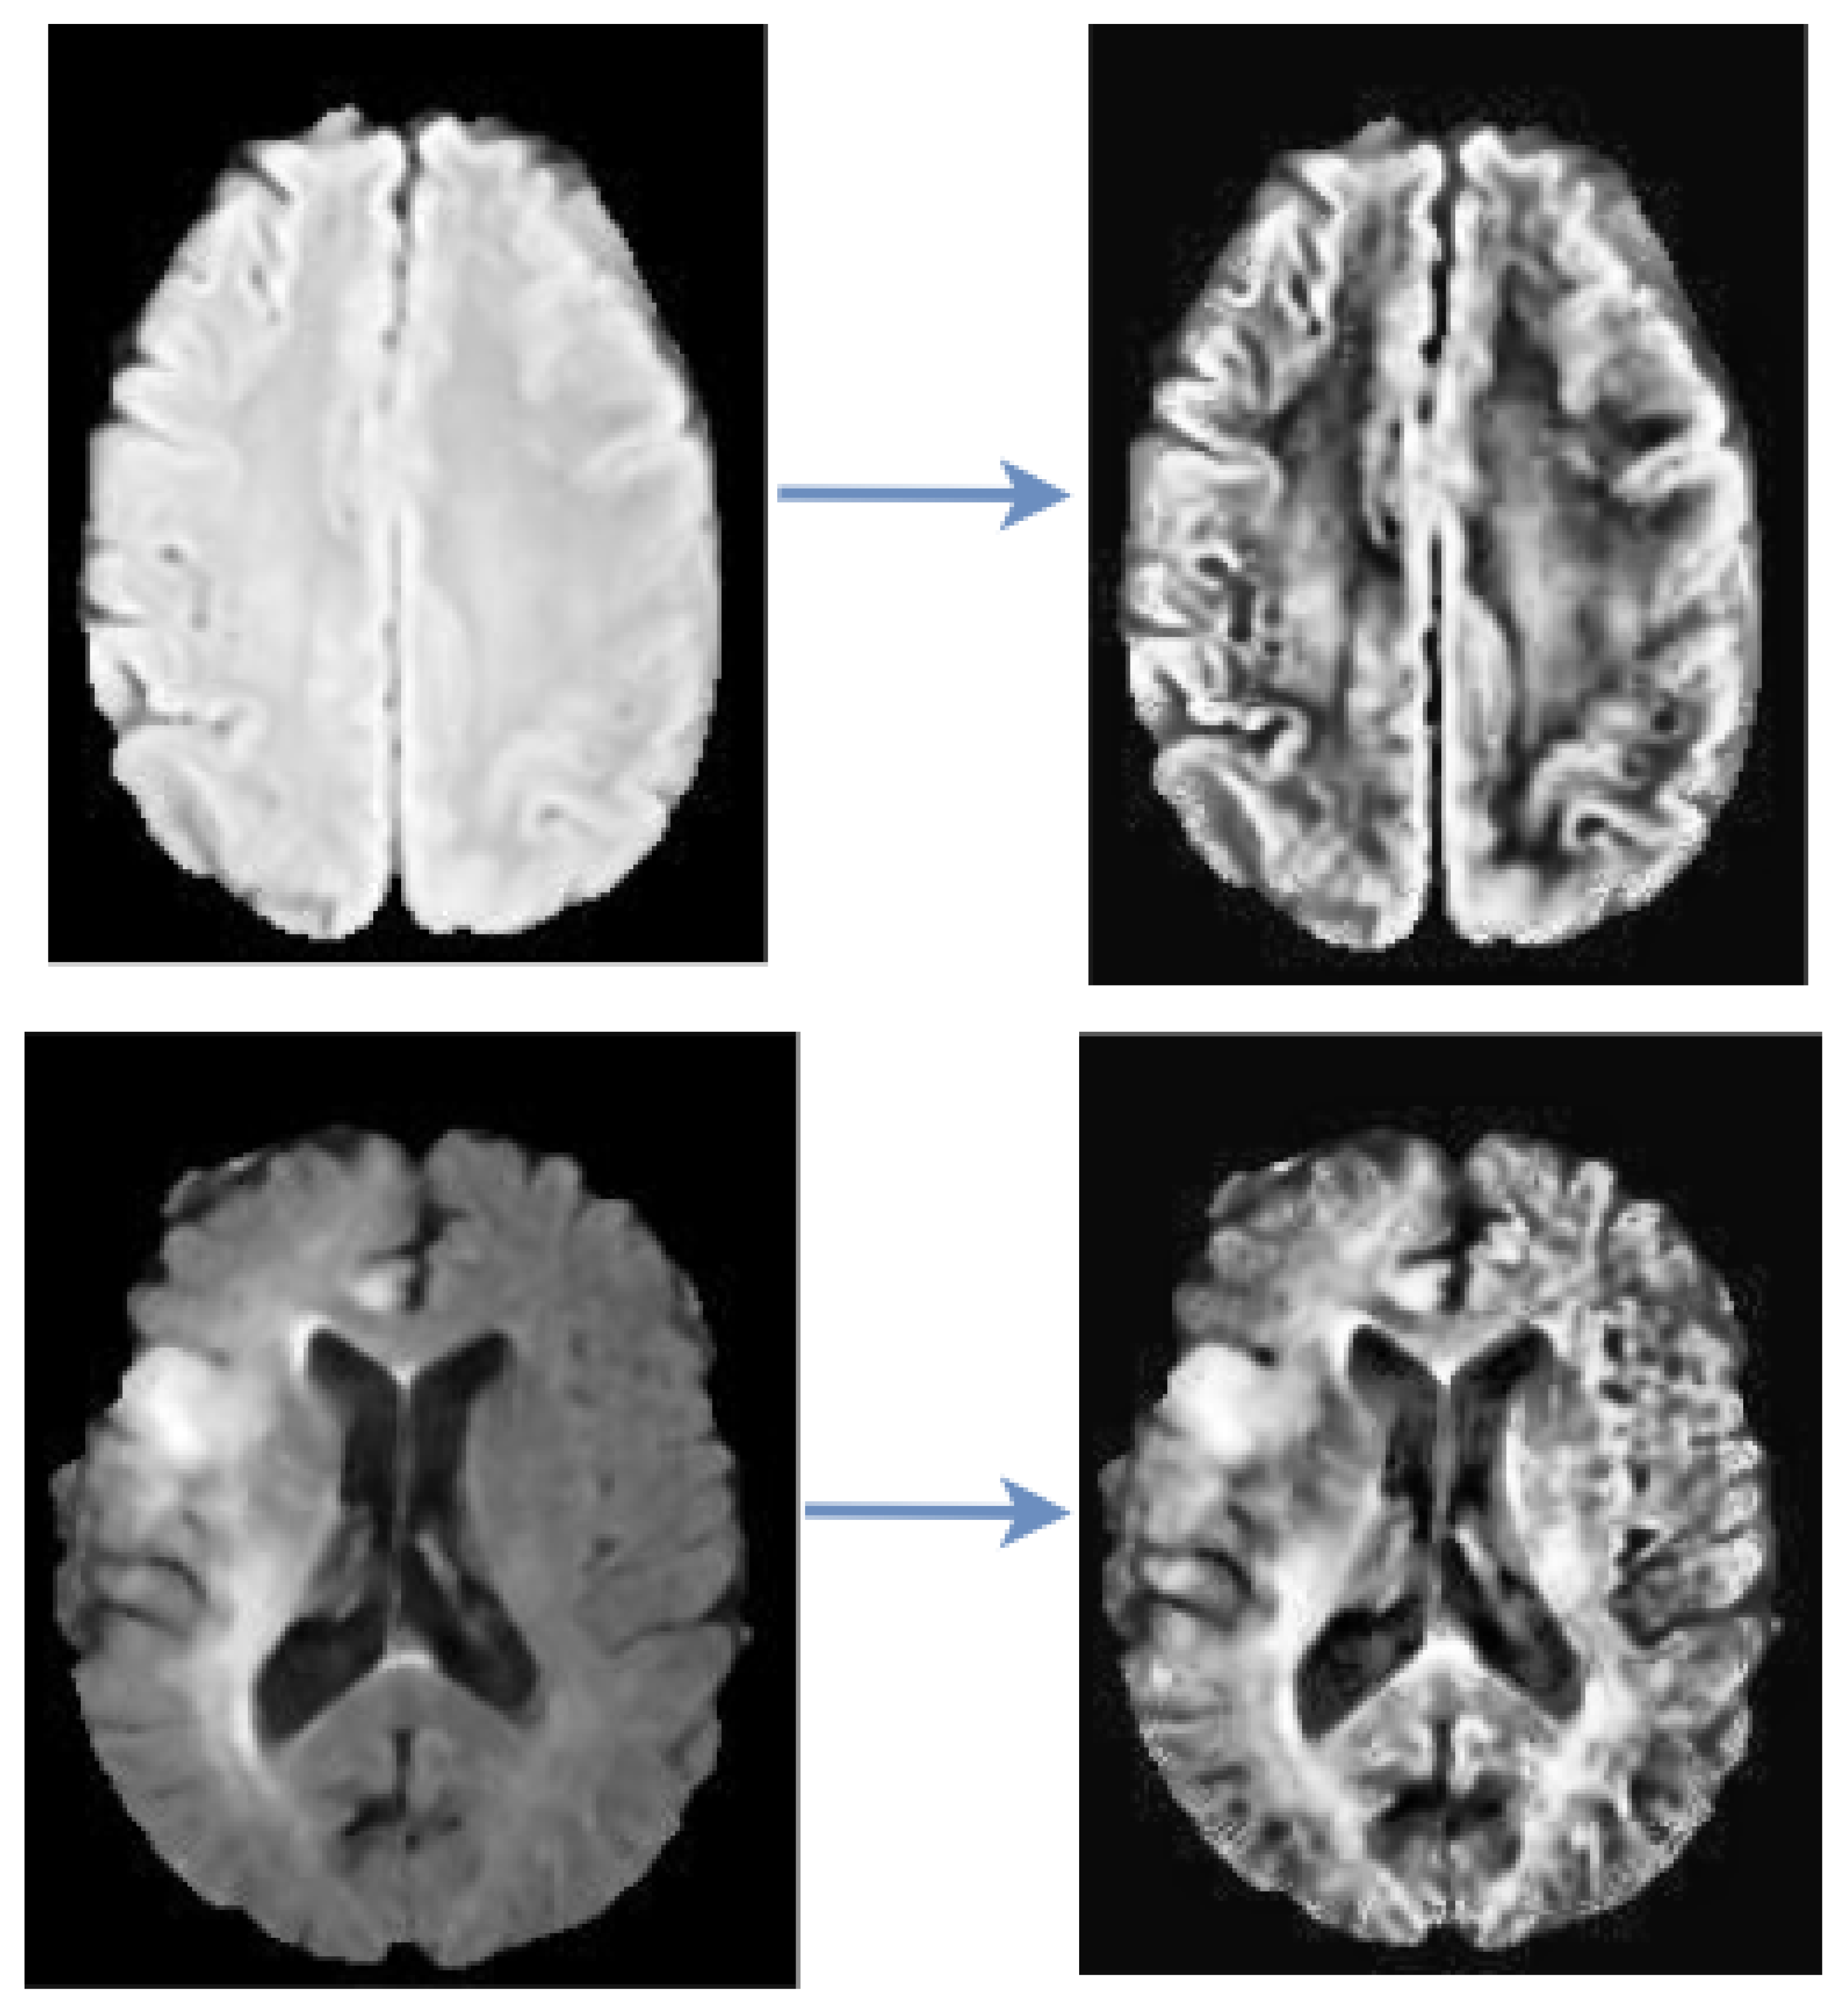

CLAHE Images

This study utilized CLAHE as a pre-processing technique to enhance the contrast and features of the image by pronouncing abnormal patterns in the image. Contrast Limited Adaptive Histogram Equalization (CLAHE) algorithm produces a more realistic appearance among the histogram equalization family and it is capable of reducing noise amplification. We have examined the efficacy of CLAHE algorithm and adopted it to the MRI dataset, as shown in Figure 2.

Figure 2. CLAHE Pre-processing. The images on the left are the raw images while the images on the right are the processed images.